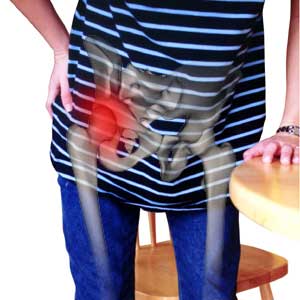

A majority of our clients this month have been coming in complaining of hip pain, deep in the socket, making it hard to walk and even causing pain in their sleep. Even Esther has been suffering from this affliction (though hers is the result of a horsing accident when she was 10 years old.)

Though many conditions result in hip pain, including those I’ve listed in the first aid stats below, we find that, just like the common complaints regarding hands, arms, neck, and shoulders — the hips can also take a beating from your computer. Well, not really your computer but rather as the result of all the sitting the average person is doing while working at their computers.

Hip pain is often more prevalent at night, waking you as you roll over or move in any way that strains the joint, but some other activities such as climbing stairs and walking for long distances can also cause it to hurt.

Many of us experience pain in our hips as the result of sitting long hours with little to no movement or due to a degenerative disease or hip injury. In all of these cases, the recommendations below, when done properly, will help to increase hip mobility, decrease inflammation and pain and let you contribute more fully to your healing process.